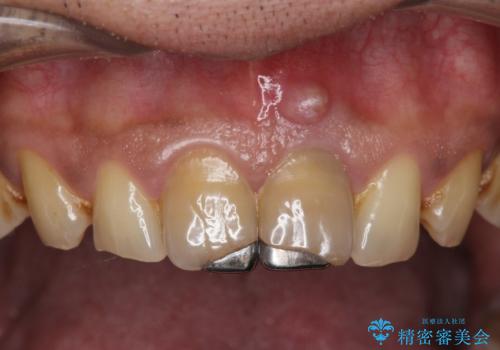

歯ぐきからの出血 膿が出る 前歯根管・セラミック治療

- 体調により前歯部の歯ぐきから出血や膿が出ることの改善を求めて来院されました。

X線写真より、根尖部に透過像が認められ根管治療・ファイバーコア築盛・セラミッククラウンの作製が必要な状態です。